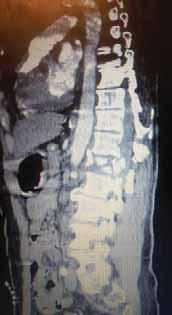

Rycina 97.9.